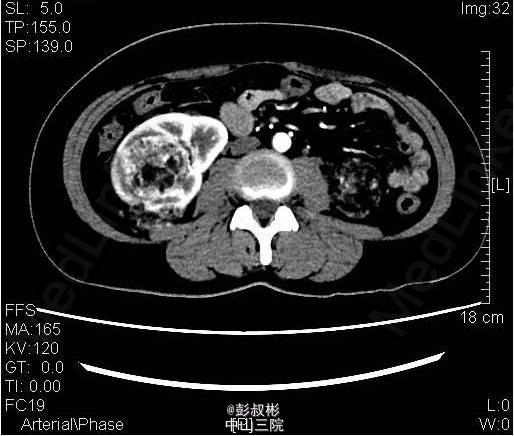

3、既往史:无特殊 4、体格检查:双肾区无红肿、隆起,左肾区叩击痛(-),右肾区叩击痛(+),左侧肋脊点、肋腰点压痛(-),右侧肋脊点、肋腰点压痛(+)。腹平软,左侧输尿管走行区压痛(-),右侧输尿管走行区压痛(-),膀胱区无膨隆,压痛阴性。 5、辅助检查:尿常规:白细胞计数27.60个/ul; 生化全套:钾3.290mmol/L;血常规:白细胞总数12.730x10E9/L,中性粒细胞绝对值9.950x10E9/L心电图、胸片正常;肿瘤抗原检查正常。ECT:右肾灌注、功能轻度降低;左肾灌注、功能基本正常。GFR:左肾为67.3ml/min,右肾为30.6ml/min。CTU:右肾体积增大,双肾可见多发大小不等结节状、团块状异常密度影,其内密度欠均匀,病灶内可见脂肪密度影,增强扫描呈不均匀强化,最大者位于右肾,约59×54mm,双肾多发错构瘤,右肾错构瘤出血。

6、入院诊断:双肾错构瘤(右肾肿物破裂出血可能) 7、处理:予心电监护、吸氧、留置尿管,引流出淡黄色尿液1600mL;急查血常规、生化未见明显异常;予抗感染、补液及营养支持治疗。拟行腹腔镜下右肾部分切除术,备右肾切除术。